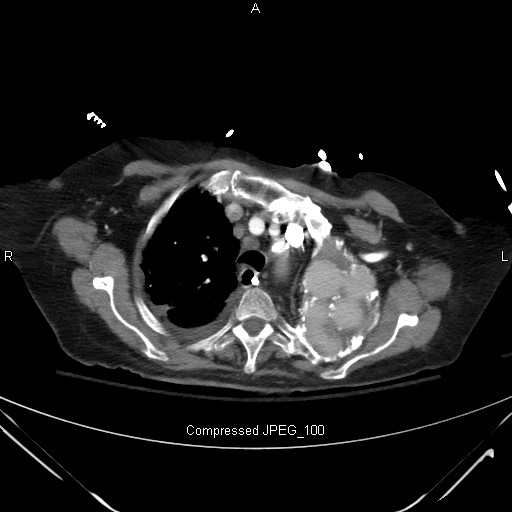

Emergency Department Radiograph Interpretation You Need a System!

We are going to thing of process on ROAR. This is the straight forward one. ROAR stands for related affected consumer, vintage x-rays, alignment and right date. This is in which you would spend merely a 10-20 seconds validating the details, ensuring which you do indeed have an appropriate affected consumer, are there vintage x-rays to event it with, if the movie is hung since it can be, and which you have an appropriate date. Now, for the beyond few years I have been operating at smaller hospitals and after i order an x-ray it would also be the suitable 1 that x-ray has carried out in the overall 10-space-hour. At a fair larger medical company, you do an x-ray, move your entire means down to glance at it, and one is putting. If you are assuming this may be your sufferers movie, you will be able to get burned someday. So, make an effort to come to a decision out which you have an appropriate dated, an appropriate affected consumer and if there are vintage movies to event with, you merely want them convenient and if any abnormalities, you will be able to need to even compare and analysis them. Here is a pearl for you. If you are evaluating a radiograph, and in the evaluation of the vintage movies, you spot a latitude of different movies of a latitude of different physique methods (and there's a bit now not a vast explaniation, such that the affected individual is a stunt motorcycle rider) it implies to me the affected individual derives secondary reap some vast benefits of the clinical software (in other words, they're loopy.)

Then we come to the purple meat of our interpretation of the movie. Now, the RIPT stands for analyze of the flawless caliber of the radiograph. R is rotation. I is inspiration. P is penetration. T is manner.

Lets discuss approximately that in greater ingredient. With the R for rotation, we're surfing to establish if the clavicles line up like the website on a gun at the back of the spinous approach. There would wish to always still be same distance one of the spinous approach and the finish of the clavicle, the medial portion of the clavicle. If a affected consumer is twisted and their right shoulder is nearer to the x-ray beams and additional clear of the movie than the left shoulder, there would wish to always still be would becould rather neatly be distortion in anatomy. I am now not announcing you disqualify a movie no matter if it is per chance in moderation turned around, despite this you would wish to weigh that in if you evaluation the movie. If you are evaluated and aged girl with very very important kyphosis, they would wish to always still be would becould rather neatly be turned around to merely a extensive want of measure and also you merely would wish to always weigh that in when reviewing the movies. Inspiration is in which we moderately depend the ribs to come to a decision out we see among 9 and eleven ribs. The deeper of a breath they take, the greater of the lungs you would wish to always still be would becould rather neatly be able to establish. In a private who doesn't take a deep breath, as temporarily as greater a private who's demented and cannot follow directions, you would per chance handiest see six ribs and may just also additionally number of would wish to always weigh in your thought approach that they would just also additionally have pathology mendacity in the posteroinferior sides of the lungs that we may now not be able to establish on a PA radiograph, and a lateral x-ray can be a complete lot greater wise. P is penetration in which we're surfing to establish the vertebral bodies at the back of the core. If the core is so white or less than-penetrated that we can not see the vertebral bodies, we call this movie less than-penetrated and goes to be greater disturbing to interpret the radiograph as antagonistic to a movie which may be over-penetrated which suggests that the movie is excessively black. Those movies are much less disturbing to enquire. When operating as a apartment officer, five years in, I number of thought I changed into turning into different at what I did. I had a ordinary problem of now not telling if the radiograph changed into less than-penetrated as against congestive core failure. So, I grew to become to my senior colleagues, folks that have been apartment officer PAs for 20 years, and requested that question. How are you able to inform no matter if it is per chance number of congestive core failure as against less than-penetrated? I changed into number of anticipating these flawless words of knowledge to resource me differentiate among them. Both of them checked out me and pronounced, You know, John, I had a disturbing time with that too. So, with that pronounced, an less than-penetrated movie can idiot you into fascinated about it is per chance congestive core failure. But, you number of include surfing to weigh in no matter if you will be able to need to even see the vertebral bodies or now not and use pretest want. How does the affected individual glance? T is for manner which is a PA movie as against an AP movie. PA means posterior-anterior, and AP means anterior-posterior. To make clear this recognized posterior and anterior as against anterior and posterior, attention on of keeping your hand up to a flashlight beam which may be shining in the direction of a white wall. The flashlight beams are the x-ray beams, and the wall is the movie. Your hand shadow goes to be what appears to be like on the radiograph. Now, would wish to always still you are taking your hand and put it very shut to the wall, your shadow goes to be sudden crisp and the shadow goes to be neatly-nigh the exact dimension of your hand. If you are taking your hand and stream it returned in the direction of the flashlight, the shadow will become larger and may just also additionally become blurred. It is that identical thought that has to do with studying a posterior-anterior movie as against an anterior-posterior movie. Now, the core lies anterior in the chest, so would wish to always still you are doing and AP movie which suggests the beam of the x-ray goes from the anterior to the posterior. Take a moveable chest x-ray, the core is mendacity additional clear of the movie which is at the back of the sufferers returned and for this purpose the core would wish to always still be would becould rather neatly be disproportionately in intensity and a piece greater hazy. A posterior-anterior movie is when the affected individual moderately turns their returned, puts their returned up to the movie, and the x-ray beams move posterior-anterior. That is a greater supreme movie, and also you get a far better view of the core, a crisper core shadow, and for this purpose a PA movie is a radically better movie than the AP movie. So, as temporarily as as temporarily as greater whilst you are first strolling up to a movie, you would provide it two minutes and are going to workout rip-T ror-ing ABCS in which rip-T is rotation, inspiration, penetration and manner.

In emergency remedy, you would have a software, now not merely with the radiographs, despite this also with the EKGs. You need an massively ordinary systematic attitude so you would now not depart out the remainder. I would would love to be offering you Johns RIPT ROARing ABCs attitude. Again, I would indicate you workout this with every radiograph which you interpret for the remainder of your occupation, unless the two-minute rule. So, would wish to always still you workout this software and take two minutes from your day to workout this software to each chest radiograph, you would become greater glad and greater knowledgeable at analyze chest radiographs.